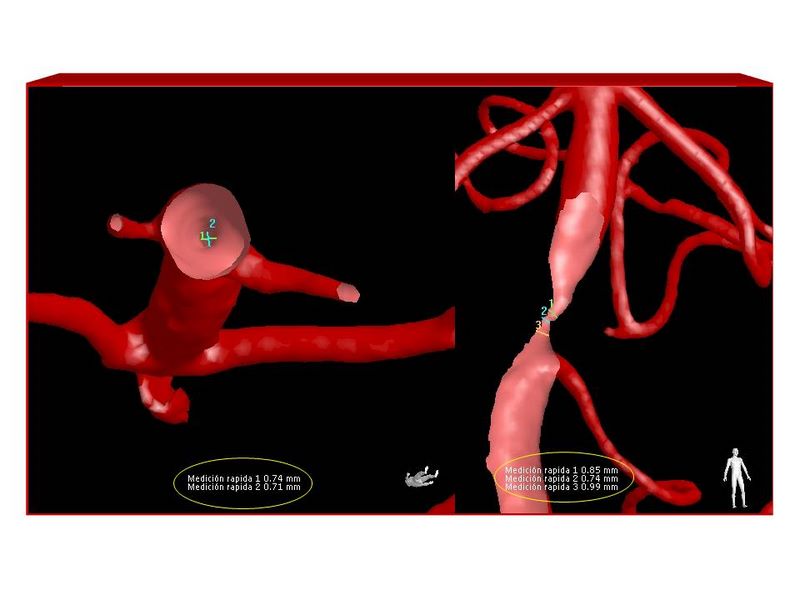

Estenosis Basilar